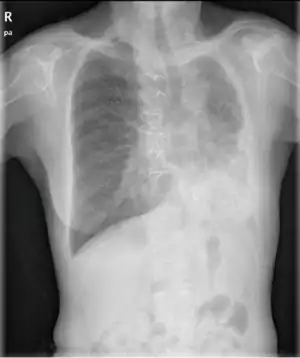

| Chest radiograph of a woman with unilateral pulmonary agenesis | |

- Chest X-ray is effective in detecting the traits of lung herniation.[1] The unaffected side of lung tends to undergo hypertrophy, and move towards the empty space in the chest wall on the opposite side.[1] This herniation could be indicated by fluoroscopy.[1] With age increasing, the herniation progresses and ease its detection.[1]

- Electrocardiogram is useful in detecting dextrocardia, a possible outcome when agenesis is present on the right lung.[1] With empty space in the chest wall, the heart rotates in clockwise direction, shifting the location for apex beat occurrence.[1] Hence cardiac physical examination also helps as heart sounds is heard best at right chest with dextrocardia.[1][4] In the condition of left side agenesis, heart sounds will appear to be louder than normal.[1][4]